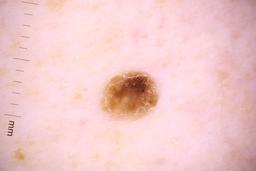

Description:

These are the images used in the paper: Analysis of the ISIC image datasets: Usage, benchmarks and recommendations

Paper Link: https://www.sciencedirect.com/science/article/pii/S1361841521003509

They have also been used by newer versions such as: Skin Lesion Classification Using Dermoscopic Images and Clinical Metadata: Insights from Multimodal Models